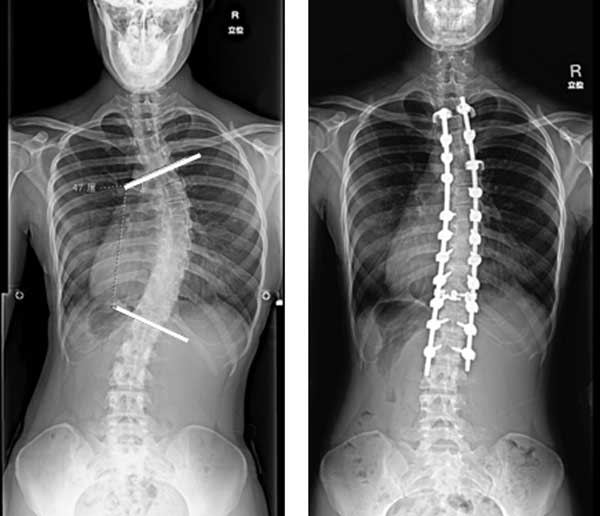

第14回 側弯症の矯正固定術脊椎手術.com。